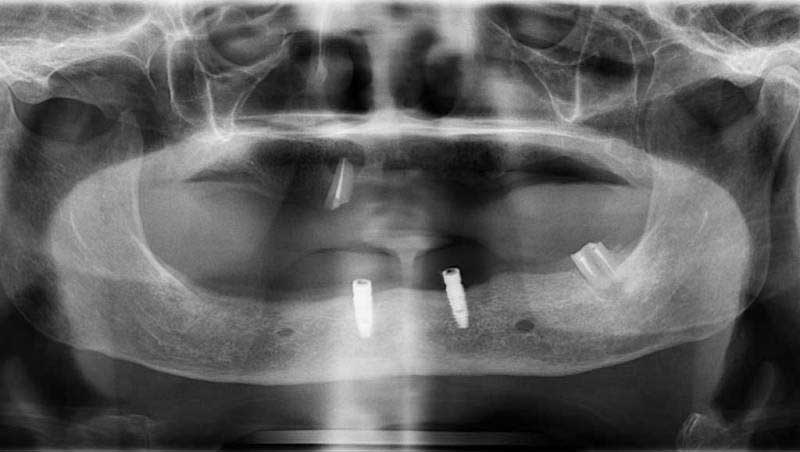

案例1